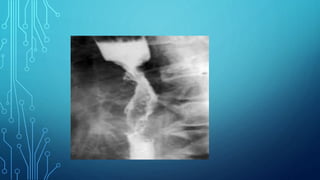

6. Fluoroscopy of the stomach: the main

symptoms are filling defect, the presence of

aperestaltic zones. Apithetic relief of the

mucous membrane, local thickening or

breakage of the folds of the mucous membrane.

Diagnostics 1. Complaints 2. Anamnesis 3.Palpation 4. Study of gastric contents 5. Blood test 6. Fluoroscopy of the stomach: the main symptoms are filling defect, the presence of aperestaltic zones. Apithetic relief of the mucous membrane, local thickening or breakage of the folds of the mucous membrane. 7. Gastroesophagoduodenoscopy 8. Biopsy